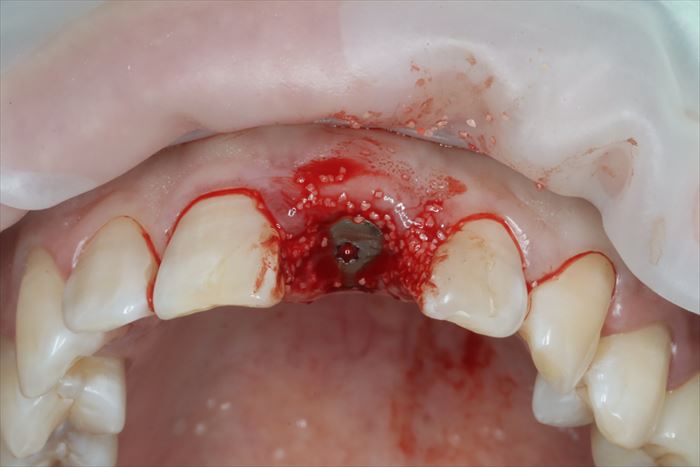

では、いよいよ仮歯を外して抜歯即時インプラント埋入オペのスタートです。

歯肉が歯根の上面をカバーするように増殖して覆い隠しています。

増殖して覆い隠している歯肉は正常像ではありませんので必要最小限切除して抜歯します。

_

抜歯時には極力周囲の歯槽骨にダメージを与えないように(非侵襲的に)慎重に抜歯します。